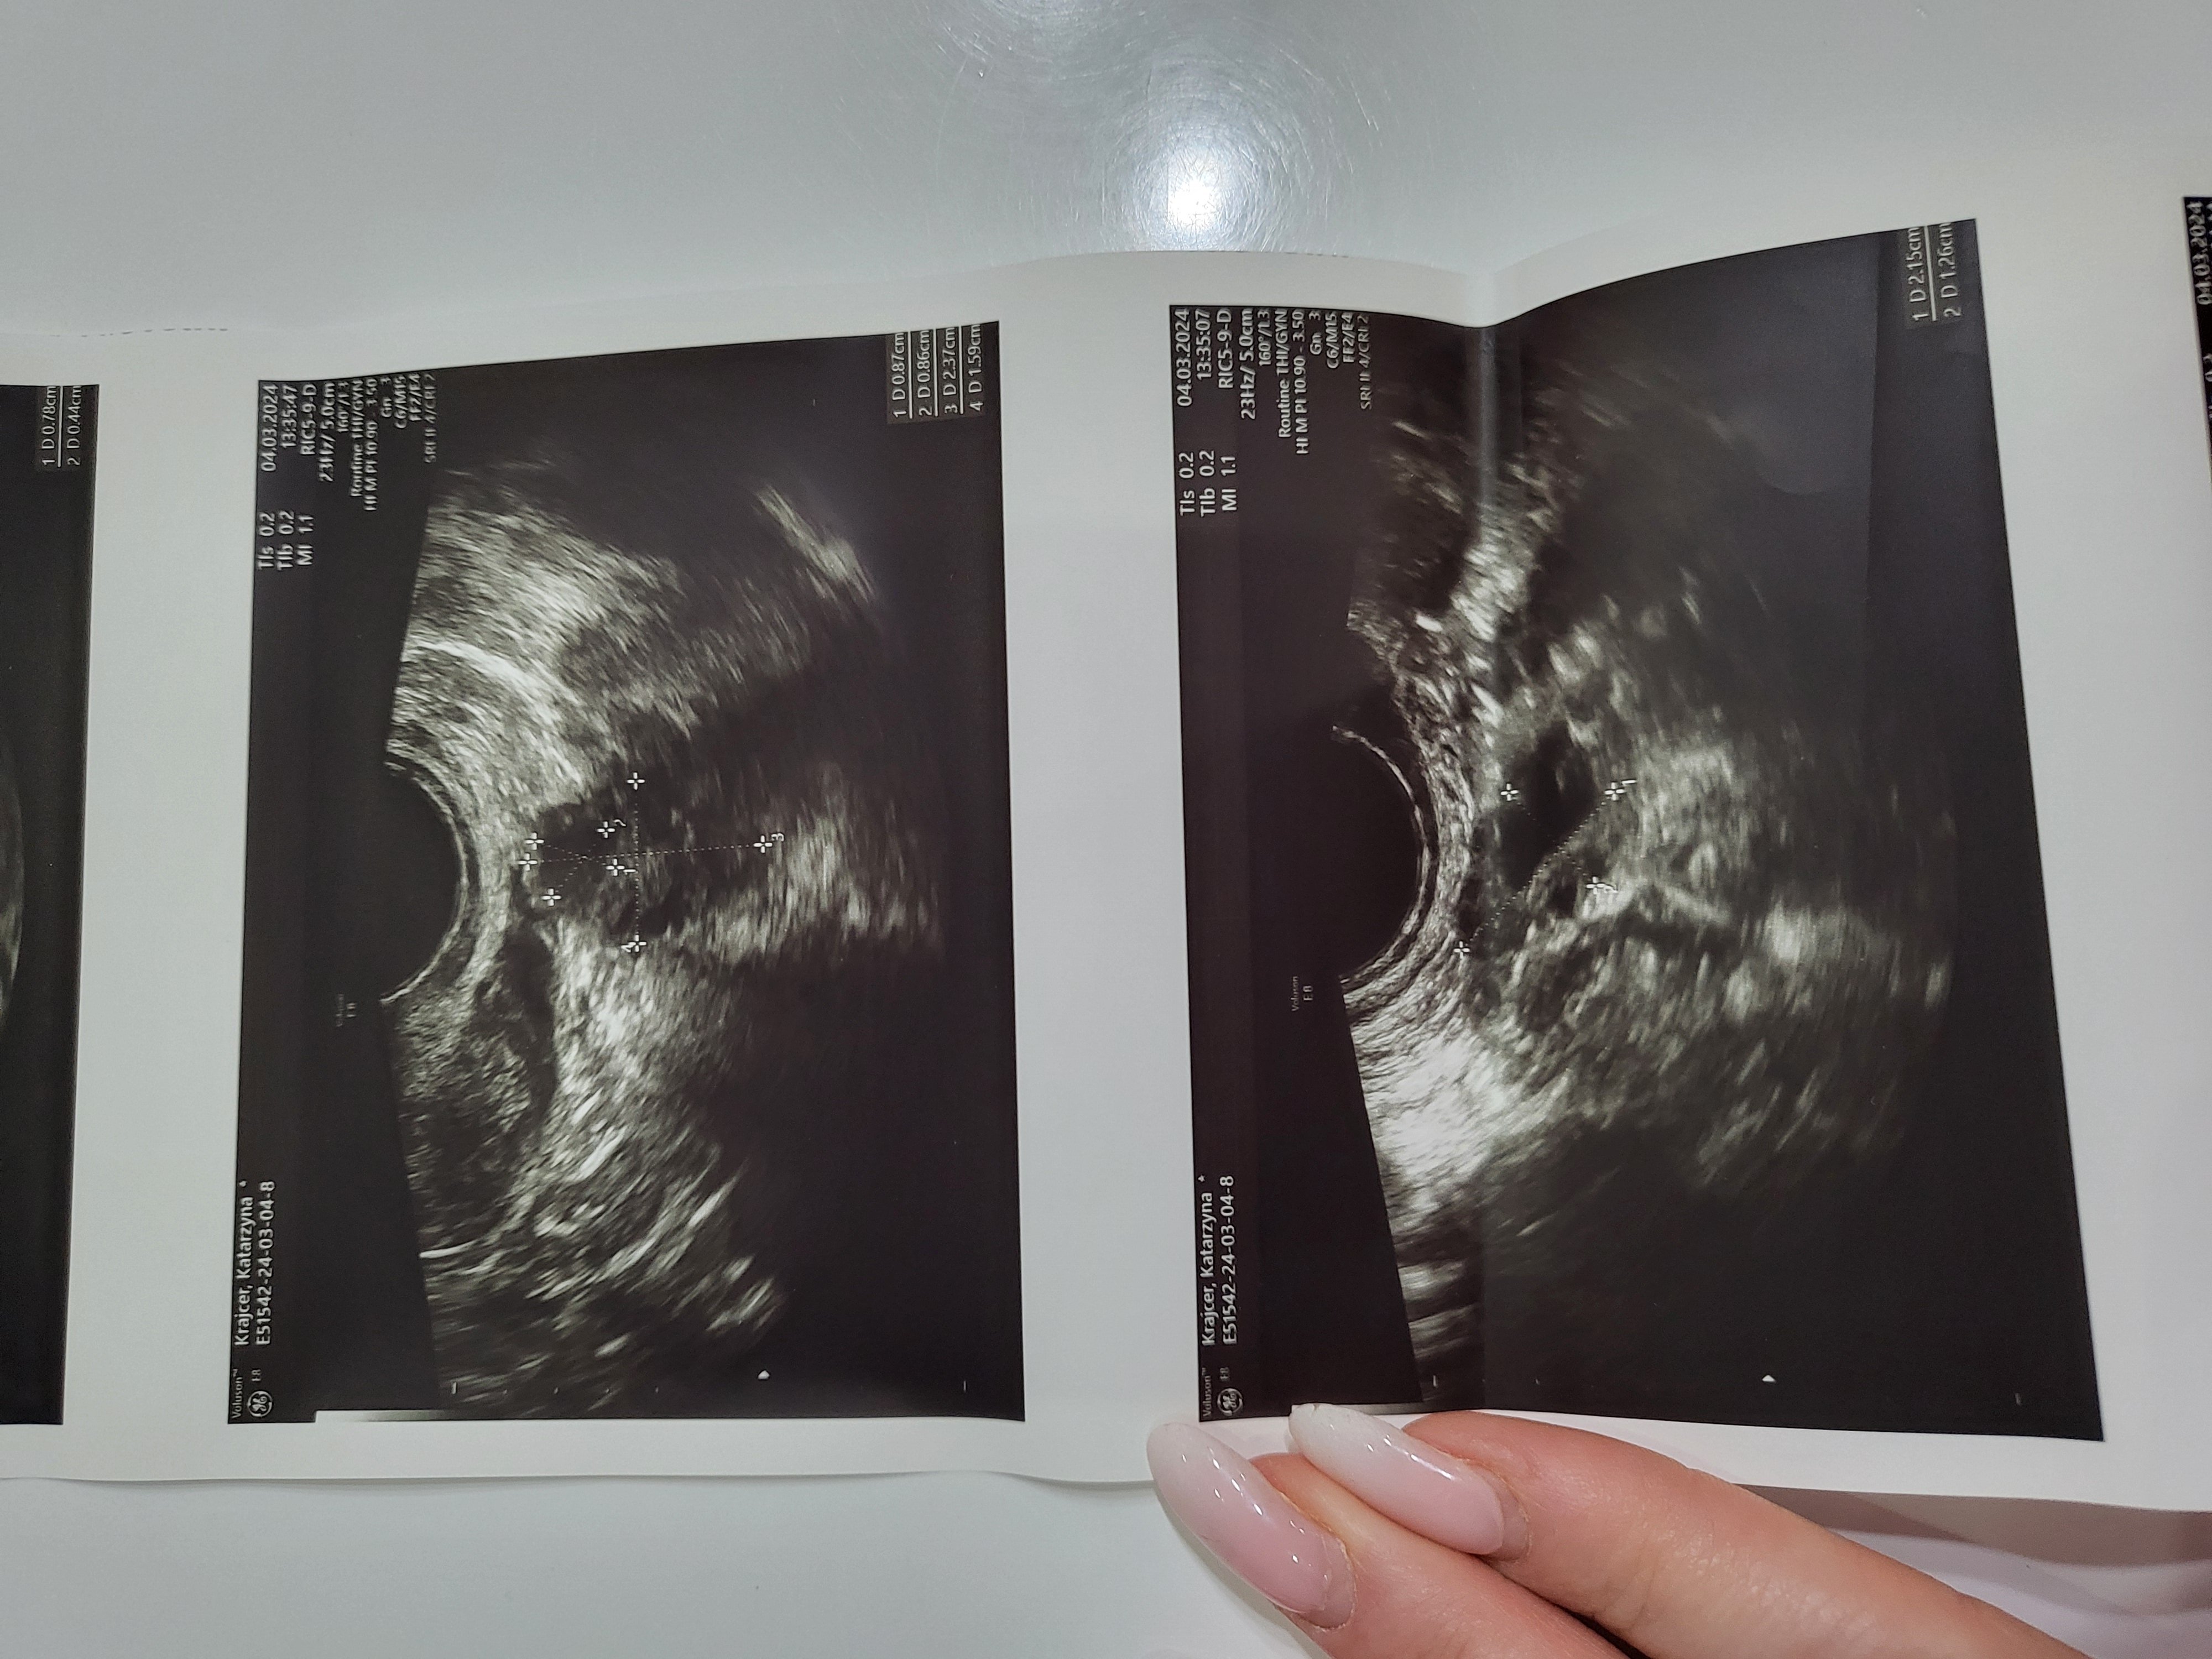

Pani doktor przy każdym USG transwaginalnym odnajdywała torbiele: mniejsze, większe, mnogie, dwukomorowe – lecz były ,, do obserwacji”. Pomimo przyjmowania tabletek hormonalnych one nadal się pojawiały. W celu diagnozy skierowano mnie na laparoskopię, która się nie odbyła ze względu na planowaną w niedługim czasie operację usunięcia dwóch przepuklin pachwinowych.

Moje wizyty u ginekologa odbywały się 1-2 razy w miesiącu, jednak cały czas słyszałam, że torbiele trzeba obserwować.

Natychmiast umówiłam się na wizytę, która potwierdziła obecność torbieli. Dostałam po raz kolejny nic nie wnoszącą radę ,, trzeba obserwować”.

Postanowiłam umówić się na wizytę, która miała miejsce 04.03.2024r.

Dr Karmowski prosił, abym usiadła na fotelu i po dokładnym przeprowadzeniu badania opowiedział o wszystkim co mi dolegało. W końcu na swojej drodze spotkałam lekarza, który chce i potrafi mi pomóc.